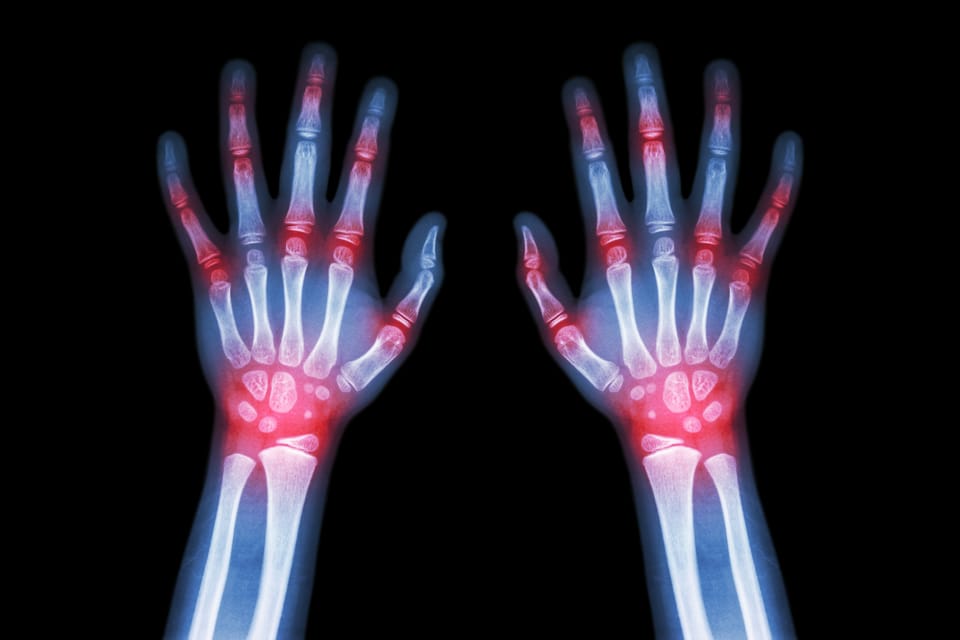

25 Jun 2025 2 min read Arthritis (Rheumatoid) Sanoviv This post is for paying subscribers only Subscribe now Already have an account? Sign in